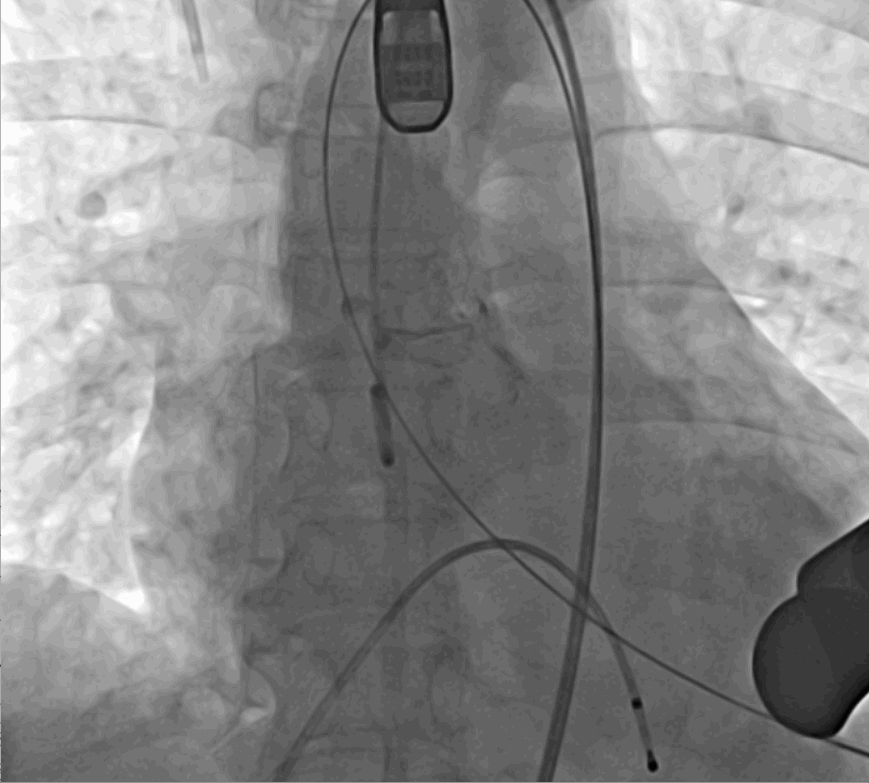

手術(shù)采用經(jīng)心尖入路,對患者進(jìn)行全麻后,在左側(cè)心尖處做3-4cm微創(chuàng)手術(shù)切口,在DSA及超聲引導(dǎo)下手術(shù)順利完成。從導(dǎo)入器械到完成瓣膜置入,僅耗時約10分鐘。術(shù)后即刻主動脈瓣返流程度由術(shù)前大量返流轉(zhuǎn)為消失,患者于導(dǎo)管室拔除氣管插管,次日由ICU轉(zhuǎn)入普通病房。

術(shù)中釋放定位鍵后DSA影像圖